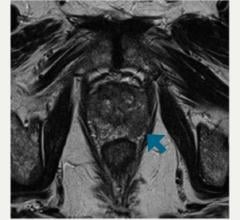

A novel magnetic resonance imaging (MRI) method that detects low levels of zinc ion can help distinguish healthy prostate tissue from cancer, UT Southwestern Medical Center radiologists have determined.